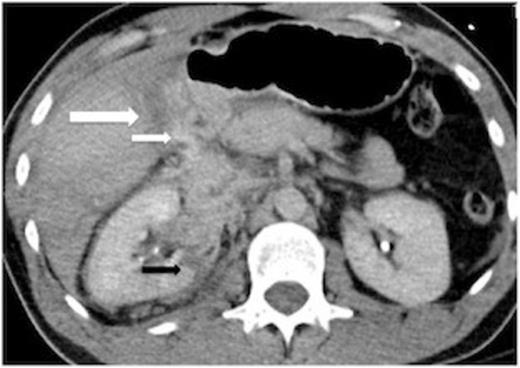

A 35-year-old male involved in a motor vehicle collision arrived haemodynamically stable to the Emergency Department complaining of abdominal pain. An abdominal CT revealed liver laceration and active contrast extravasation near the gallbladder fossa (Figure 1).

Preoperative CT scan showing a liver laceration (large white arrow) and IV contrast extravasation in proximity to the laceration (small white arrow). The normally fluid filled gallbladder is not well seen here. The right kidney is also lacerated (black arrow). There is not a large haemoperitoneum.